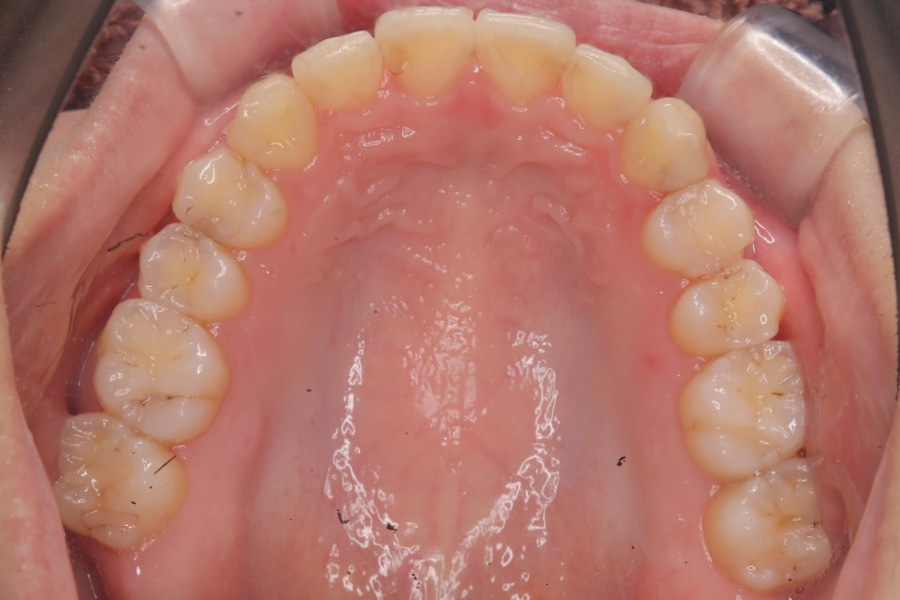

治療後